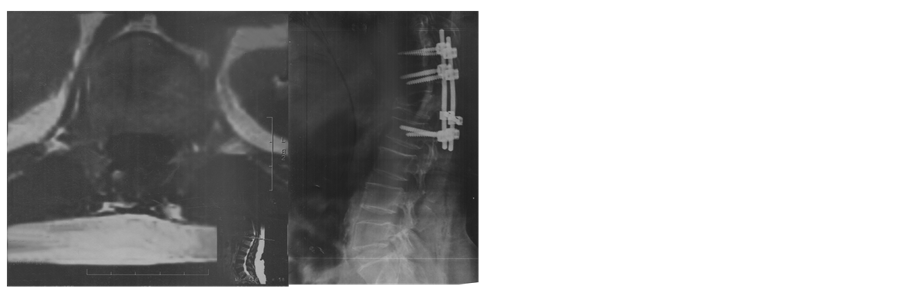

A 61-year-old female patient was with history of spinal trauma in 26 year ago. Patient fall down from height and had a traumatic L1 fracture. Patient was managed conservatively at that time as she refused surgical intervention and had no neurological deficit. Patient experienced frequent attacks of low back pain and rarely sciatic pain that was treated with analgesia. 6 months ago, the patient had a progressive heaviness in both lower limbs with urinary incontinence and visited the outpatient clinic. On examination, the patient was paraparetic with motor power grade II or III below L1. Patient had hypotheisa below L1 with diminished knee and ankle reflexes. MRI lumbar and dorsal spine showed the post-traumatic L1 fracture with a new large intra-dural mass most probably meningioma or schwnoma as shown in Figure 1. Patient operated with posterior lumbar approach including posterior L1 and D12 laminectomy. Total standard microscopic excision of the intra-dural soft tissue mass with moderate vascularity was performed successfully. A posterior D11, D12 and L2 trans-pedicular screw fusion was performed at the end of the procedure. Histopathological examination revealed multiple nodules of proliferated meningothelial cells separated by delicate fibrous tissue, with thick walled blood vessels and calcified psammoma bodies together with oval to rounded cells with oval nuclei, occasional nuclear clearing and infrequent mitosis arranges in whorly pattern with rounded calcified psamma bodies. A meningeothelial and psamomatous meningioma was reported as shown in Figure 2. The patient has smooth postoperative course with improvement of her neurological deficit with physiotherapy. 4 months after surgery, the patient was able to ambulate without assistance. On her last follow up after one year of surgery; the patient has no neurological deficit and can ambulate without assistance

Figure 1. (a) X ray lateral view shows L1 fracture; (b) X ray anteroposterior view shows L1fracture; (c) MRI lumbosacral spine T2 weighted image sagittal view shows the L1 fracture and the intradural mass; (d) MRI lumbosacral spine T1 weighted image sagittal view shows the L1 fracture and the intradural mass; (e) MRI Dorsal spine T2 weighted image sagittal view shows the L1 fracture and the intradural mass; (f) MRI lumbosacral spine T2 weighted image axial view shows the intradural mass compressing the cord; (g) X ray lateral view shows the pedicular screws; (h) X ray anteroposterior view shows the postoperative fusion.